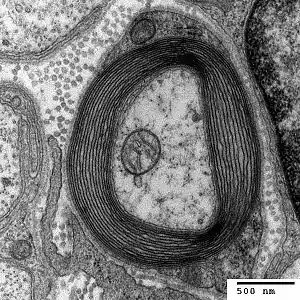

HNPP is caused by a mutation in the gene PMP22, which makes peripheral myelin protein 22. This protein has a role in the maintenance of the myelin sheath that insulates nerves, resulting in insufficient conductivity in the nerves. HNPP is part of the group of hereditary motor and sensory neuropathy (HMSN) disorders and is linked to Charcot–Marie–Tooth disease (CMT).[5]

The condition is caused by a mutation in one copy of the gene PMP22 (peripheral myelin protein 22, located at locus 17p11.2). This makes it autosomal dominant.[8] PMP22 is involved in maintaining the myelin sheath that surrounds nerves to facilitate conductivity.[5] The mutation causes haploinsufficiency, where the activity of the normal gene is insufficient to compensate for the loss of function of the other gene.[9]

The peripheral myelin protein 22 gene encodes a 22-kD protein that comprises 2 to 5% of peripheral nervous system myelin.[10]